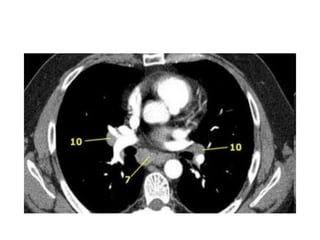

Haïch döôùi carina

• 7. Döôùi carina

7.NHOÙM HAÏCH DÖÔÙI CARINA